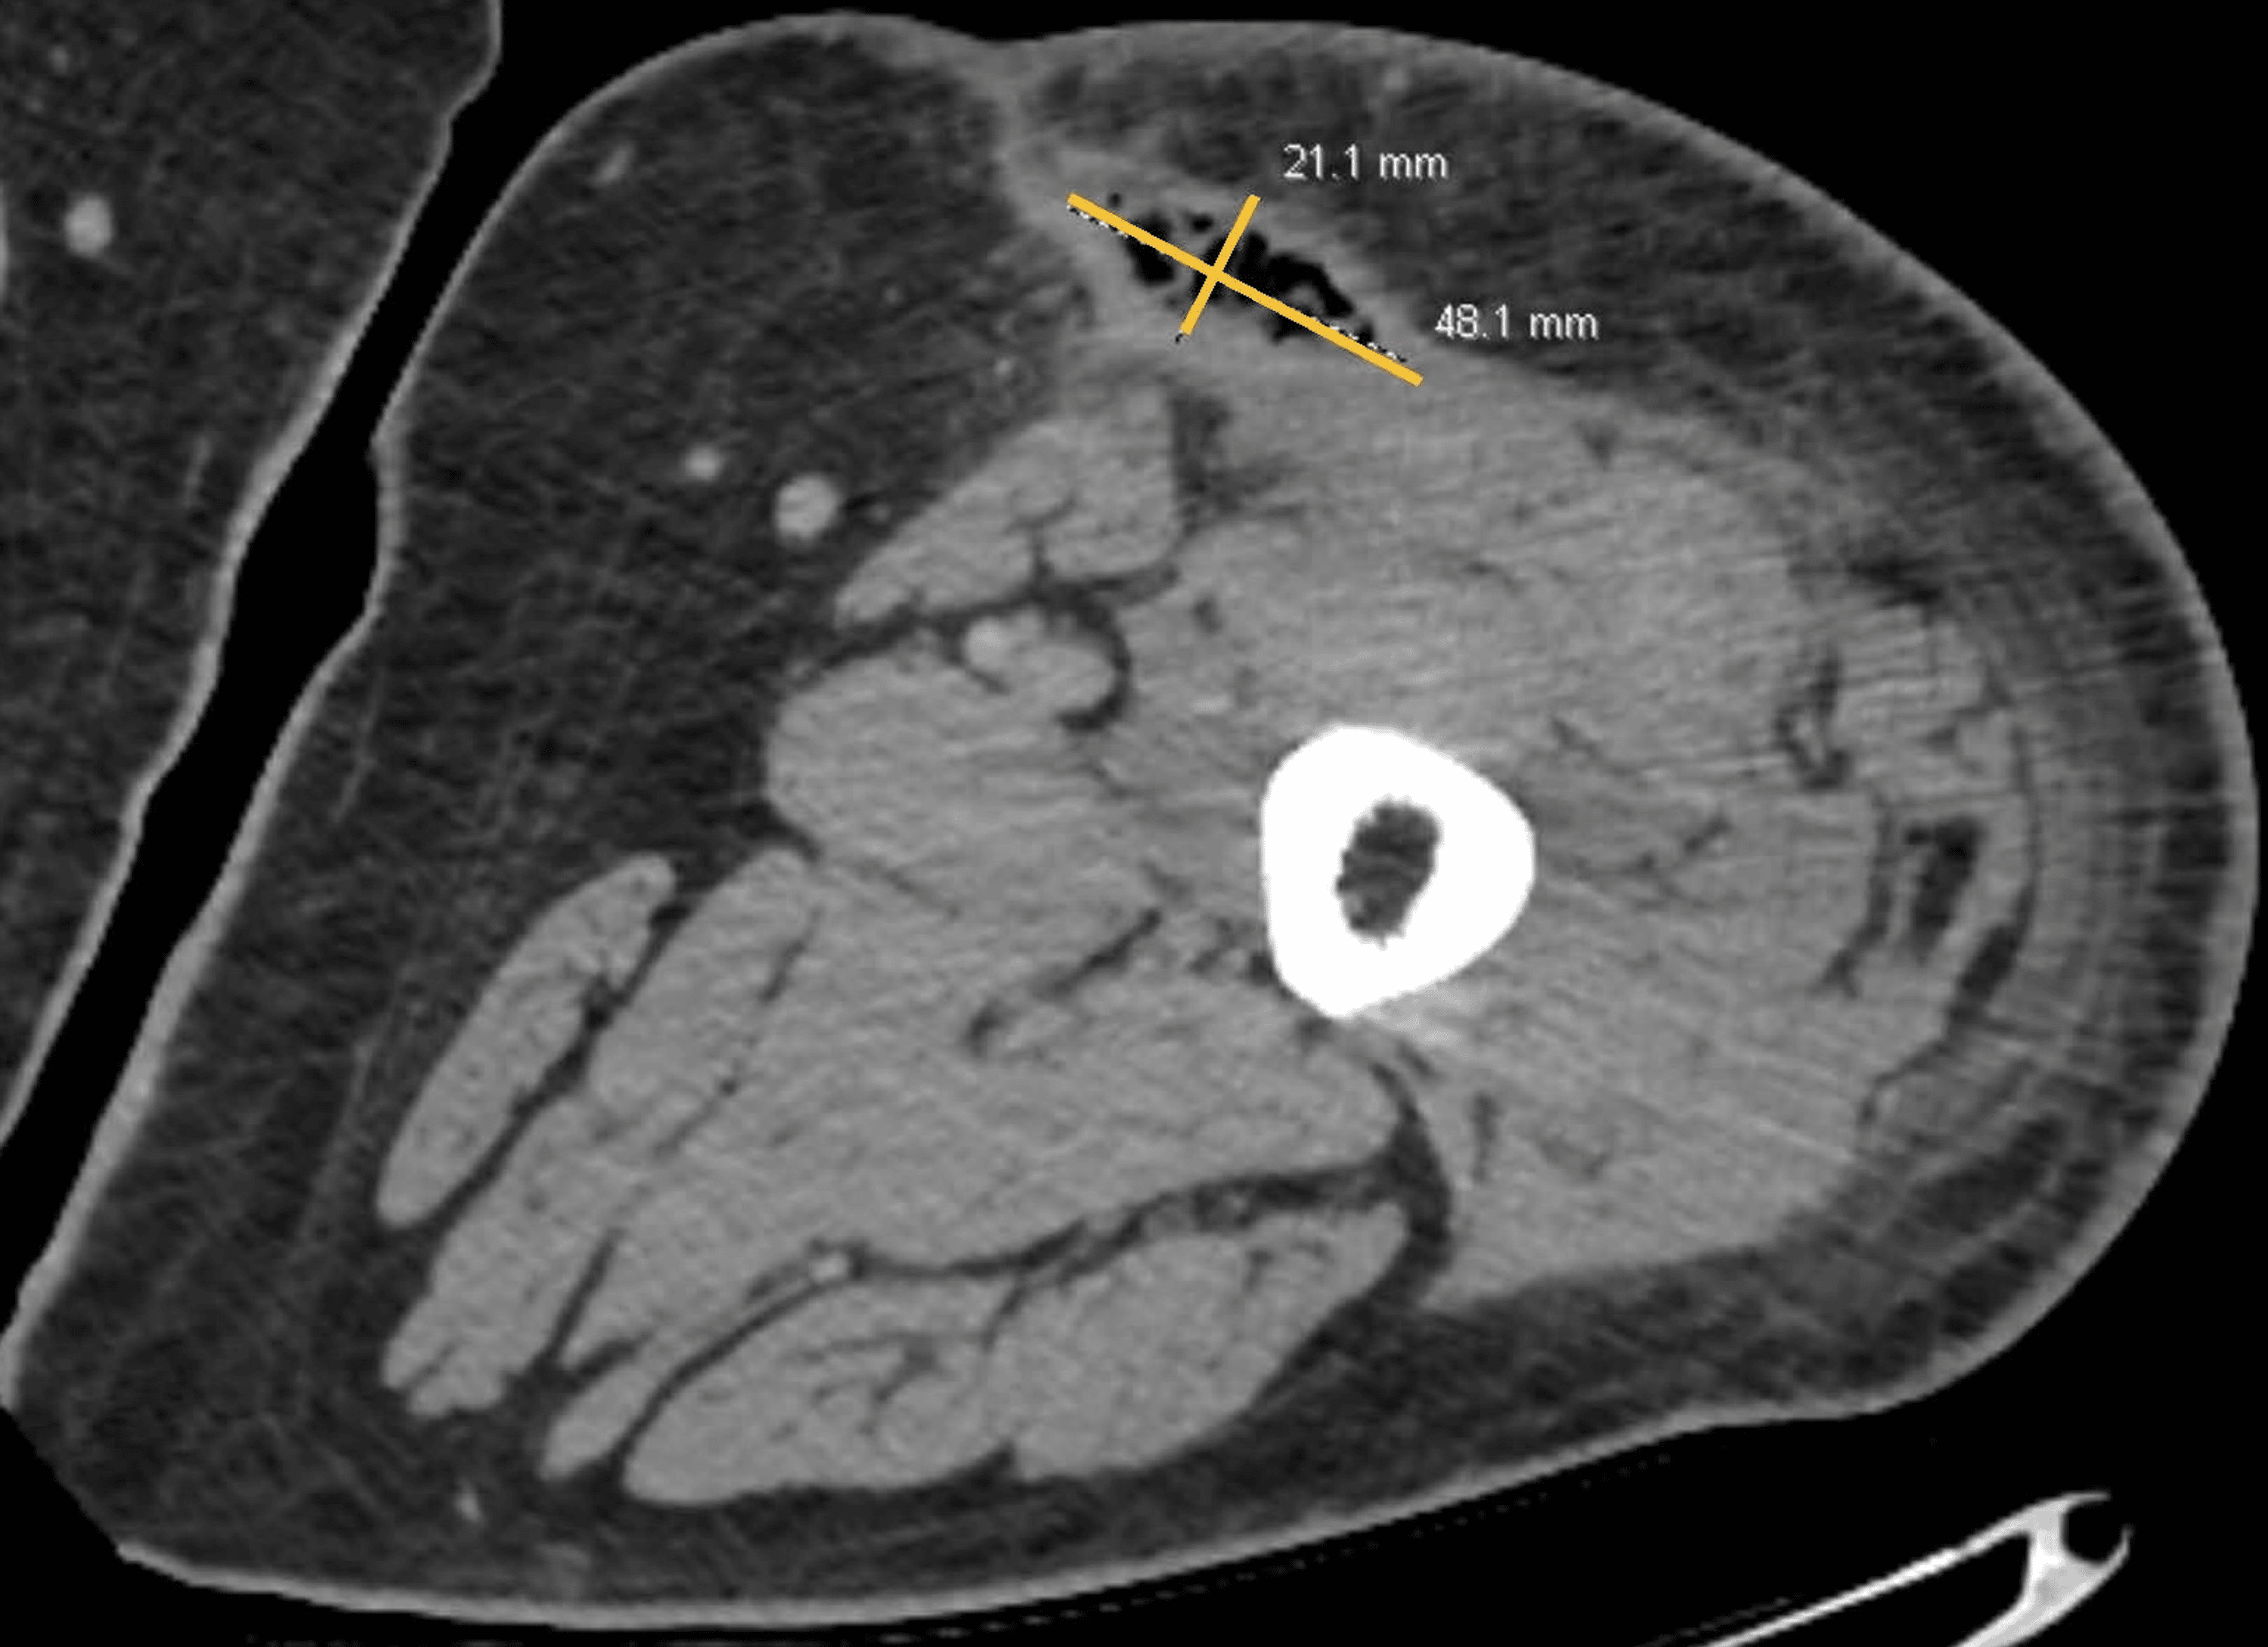

Cureus Man With PostTraumatic Leg Swelling A MorelLavallée Lesion Morel Lavallee Lesion Ct morel‐lavallée lesion is a closed soft tissue degloving injury caused by high‐energy violence, usually associated. surgical interventions such as open debridement, techniques to close. A, immediate postinjury changes can be seen in the soft tissues (asterisk). Morel Lavallee Lesion Ct.